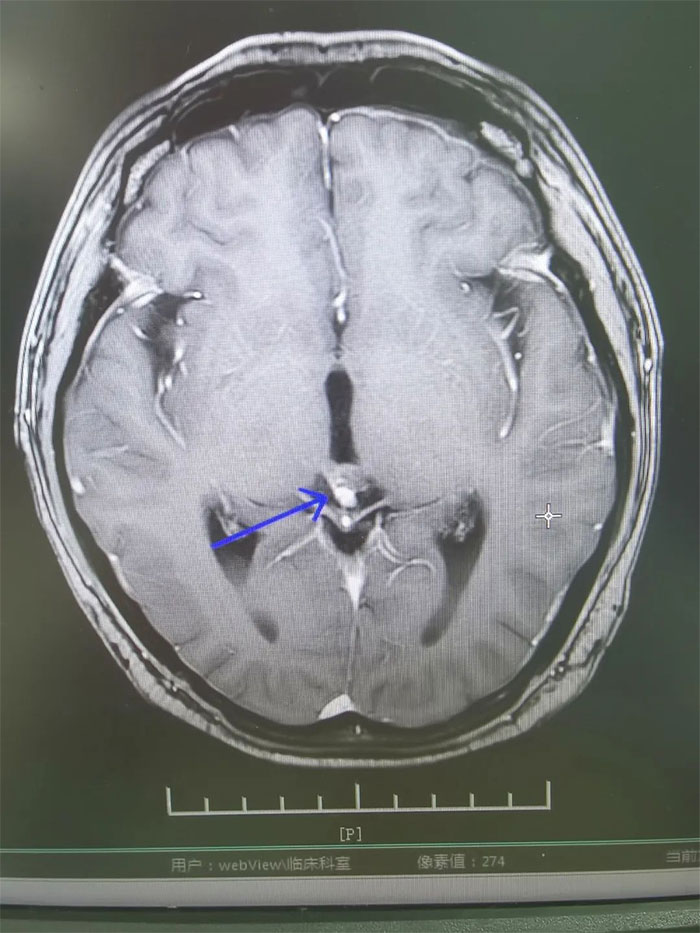

▲ 放療後複查,病灶明顯縮小

經過一個完整療程的放療,患者沒有出現明顯併發症,頭痛、噁心嘔吐症狀得到緩解。複查MRI,影像顯示病灶明顯縮小,梗阻性腦積水消失。進一步完善檢查評估後,小剛已順利出院。眼見短時間內病情即得到控制,小剛對生活又重拾信心,表示一定會以積極的心態面對人生。